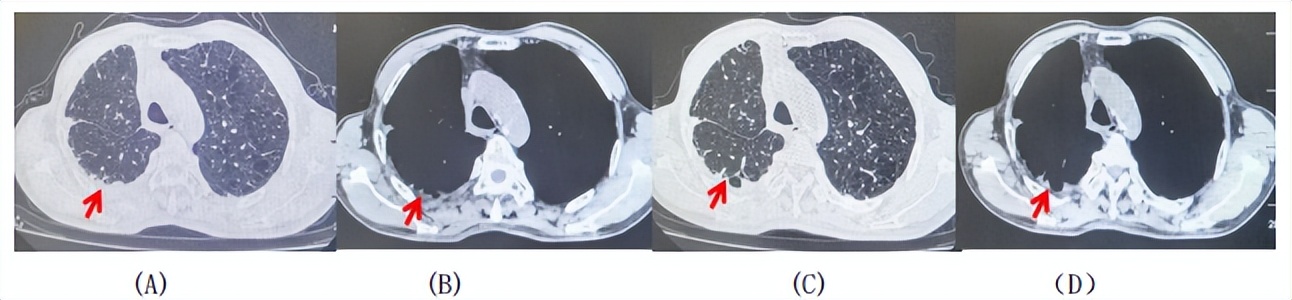

2024.09.12复查胸部CT示左侧胸膜结节,大者约为27mmx13mm,考虑转移可能性大,纵隔淋巴结增大,恶性?(如图6)。患者行胸膜穿刺活检取病理,结果示(胸膜)结合免疫组化,支持鳞状细胞癌,PD-L1(克隆号28-8)TPS约20%。分期为rT0N2bM1a IVA期,DFS为10个月。2024.09.24起行替雷利珠单抗联合紫杉醇+卡铂方案治疗4周期,复查胸CT评效SD(如图7)。后患者因脑梗塞停止治疗,于综合医院就诊,后未返院复查及治疗。

图5:患者手术前(2023.11)胸部CT肺窗及纵隔窗

图6:患者胸膜及纵隔转移(2024.09)胸部CT肺窗及纵隔窗

图7:替雷利珠单抗联合白蛋白紫杉醇+卡铂治疗4周期后(2024.12)胸部CT肺窗及纵隔窗